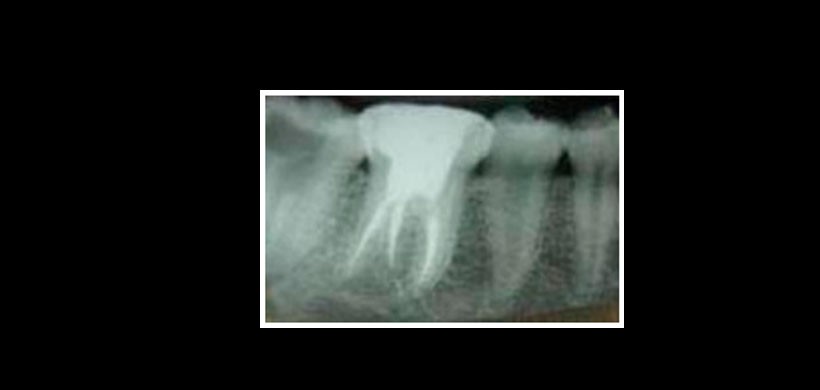

Figura 2: Radiografía inicial de la pieza 3.6.